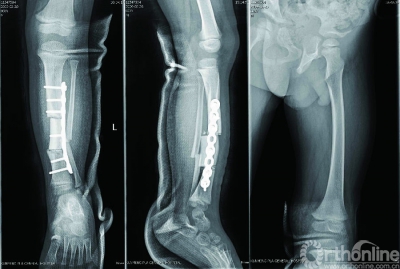

三、个性化导航模板在矫形外科手术的临床应用

我们以下肢骨骼的中心线为标准设计好畸形骨骼的理想力线,通过导航模板的媒介与患者的形态特征及生理功能取得了比较完美的一致性,术后下肢对线得到了明显的改善,并且提高了手术操作的可重复性。根据人体形态学上对称性的原理,通过对四肢力线的测量及镜像理论的应用,基于对骨骼中心线及数学方法的知识,建立了不同部位畸形矫正的个体化导航模板,在临床应用中获得了肯定的效果。

下面选择一例膝关节内翻患者做一介绍。根据镜像原理,建立患侧下肢的镜像模型,通过Three-matic6.1将模型投影到冠状面和矢状面上进行测量。我们选择对胫骨的中心线曲线上曲率最小的一段折线,其两个端点对应点的坐标定义为截骨平面所在的位置。在Three—matic6.1 软件建立健侧胫骨及其镜像模型的中心线,获得胫骨内翻角度(预期截骨角度),可以进行模拟截骨复位,设计个体化矫形方案,生成模板实体指导手术(图16-19)。

结果,术后形态学上术前均存在明显的下肢畸形,术后有了明显的改善。术后影像学测量,单平面骨骼解剖轴和矫正轴线最大偏移3.3°,手术前后双下肢长度最大相差0.5cm,手术前后测量下肢力线相比较没有显著性差异 ( P > 0.05 )。

术中操作,利用克氏针沿导航管道钻出截骨轨道进行截骨、复位、内固定;

术后X影像表现,胫骨轴线得到纠正,形态学上的显畸形得到有效纠正。

研究表明,建立的辅助精确手术的方法能够充分利用骨骼对应力的适应性控制,在矫正骨骼畸形的同时有利于骨的生长与吸收,促进骨骼愈合改建及功能优化重建。对个体化骨骼矫形的术前规划和术后评估具有了极大的启示作用。本文基于畸形骨骼的中心线及其投影,以数字化和量化的数学方法来精确的计算出截骨平面及其角度,保证了实现对畸形骨骼精准矫形的最终目的。